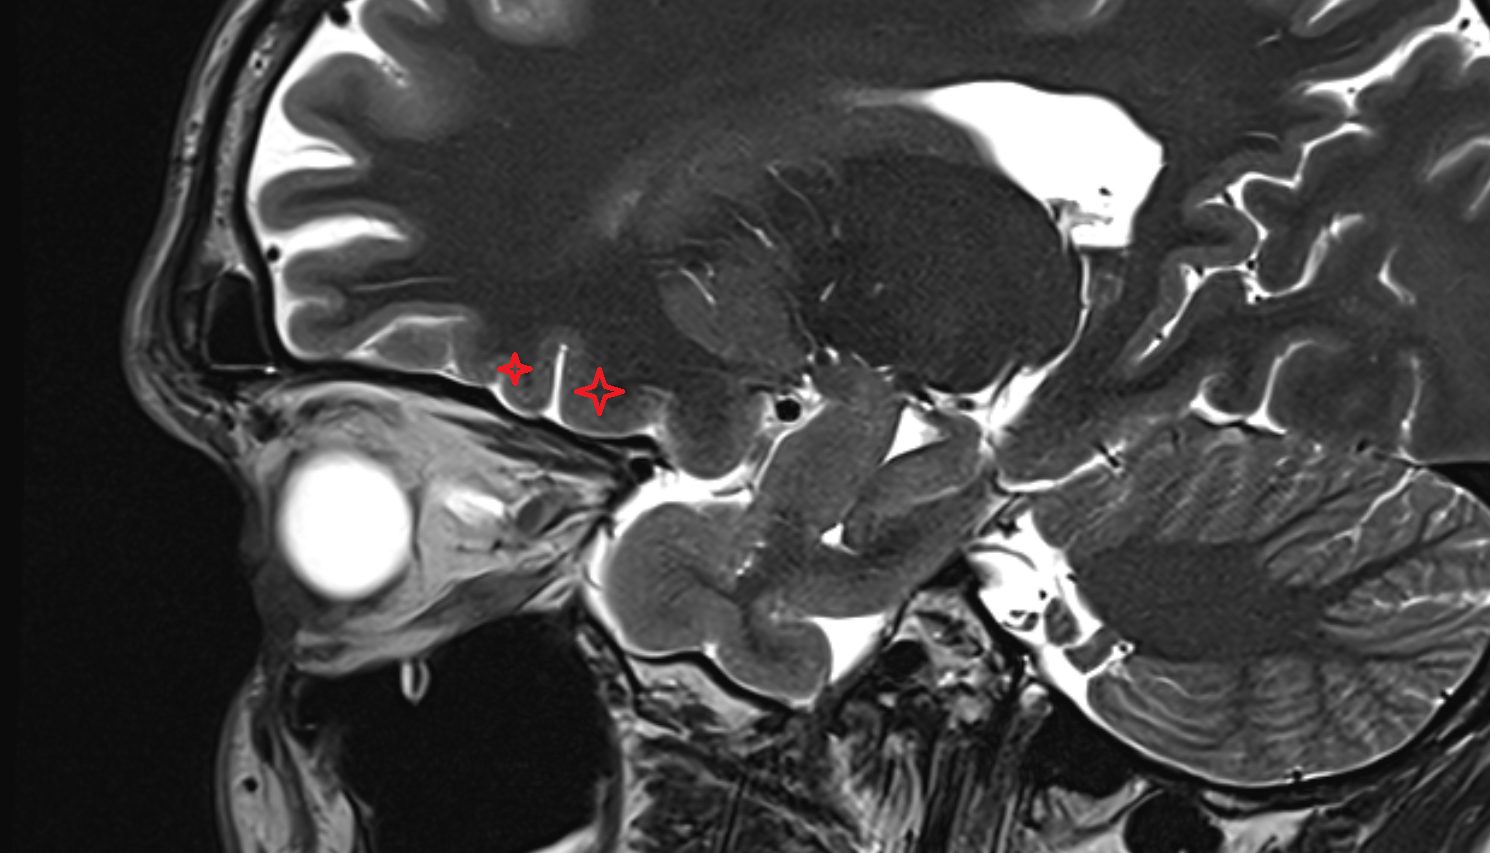

- Pituitary stalk